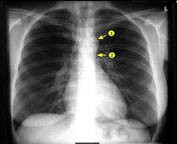

Ακτινολογικό

Το ακτινολογικό τμήμα λειτουργεί εξολοκλήρου με ψηφιακά μηχανήματα τελευταίας γενιάς για την καλλίτερη επεξεργασία και επικόνιση των ακτινογραφιών .